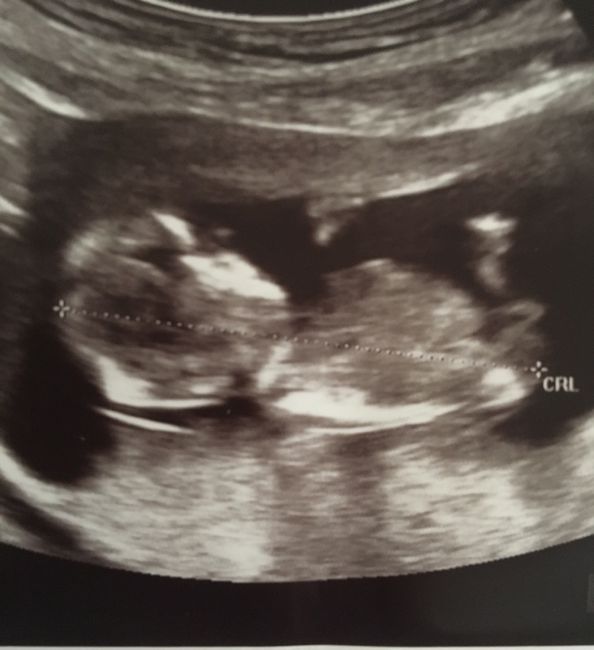

Teoria nub

Da Veronica , Il 20 Luglio 2019 alle 17:50

Buona sera,sono alla tredicesima settimana, ho scoperto da pochi giorni la teoria nub, secondo la quale si riuscirebbe a stabilire il sesso del nascituro. Chi di voi ha...